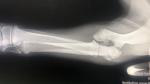

关节肘头与冠状骨斜骨折。经两个小时手术,将断骨联结